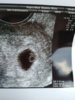

@Mimi2330, ale już duży dzidziuś ja następne podglądanie dopiero 9 maja, jak byłam w poniedziałek to sytuacja wyglądała tak :)

18136451_1826903410963163_829149997_n.jpg

70,6 KB · Wyświetleń: 59